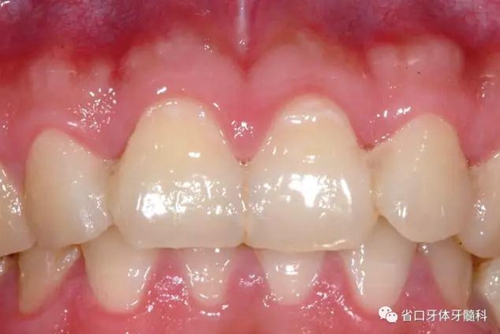

圖8:隨訪口內(nèi)照

圖9:隨訪口內(nèi)照

檢查:口腔衛(wèi)生良好,牙齦無紅腫,12-22固位良好,無松動,叩診無明顯不適,電活力測試21活力值同正常對照牙,活力值為5;